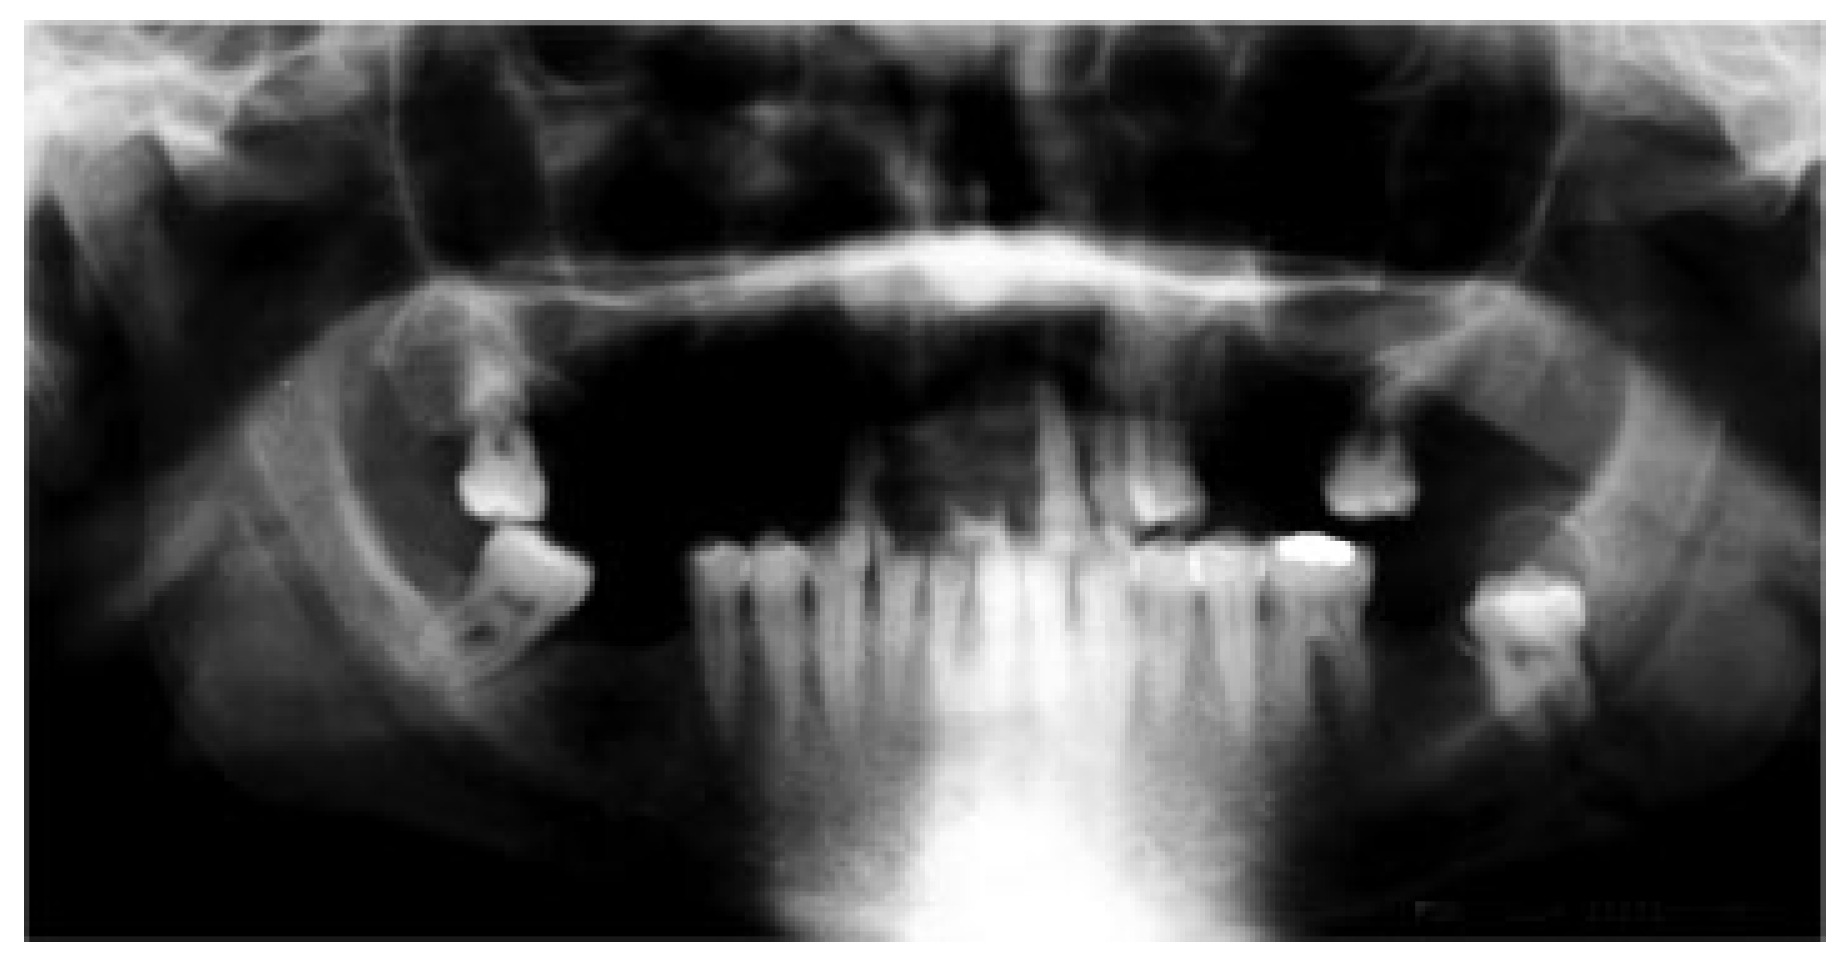

1.1. Case 1